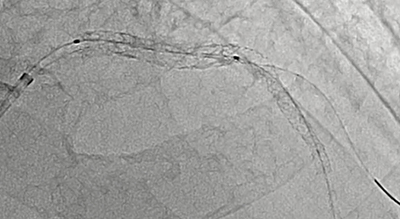

図1 Alphenixによる撮影像

イメージングチェーンの刷新により、低線量で高画質な画像を実現。